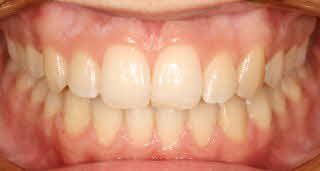

Um die Behandlung zu dokumentieren und für die Beratung der Patienten fertigen wir routinemäßig vor, nach und manchmal auf während der Behandlung Fotos von den Zähnen an.

Intraorales Bild02 [320x200] Intraorales Bild03 [320x200]